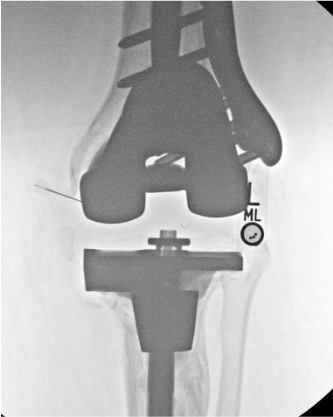

Knee

Needle placementPost-injection